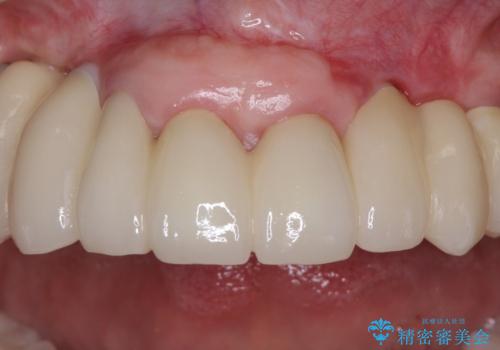

歯を抜かないといけない部分はインプラントとオールセラミッククラウンにより咬合を回復させ、歯周外科処置を行う歯については、同じくオールセラミッククラウンにて補綴治療を行うこととしました。

外科処置を多く行ったため、その待ち時間が長くかかり、さらには途中矯正治療も行なったので、治療期間は長期間となりました。

痛みには強い方であったため、治療はそれほど苦痛とは感じられず、毎回楽しく通院してくださいました。